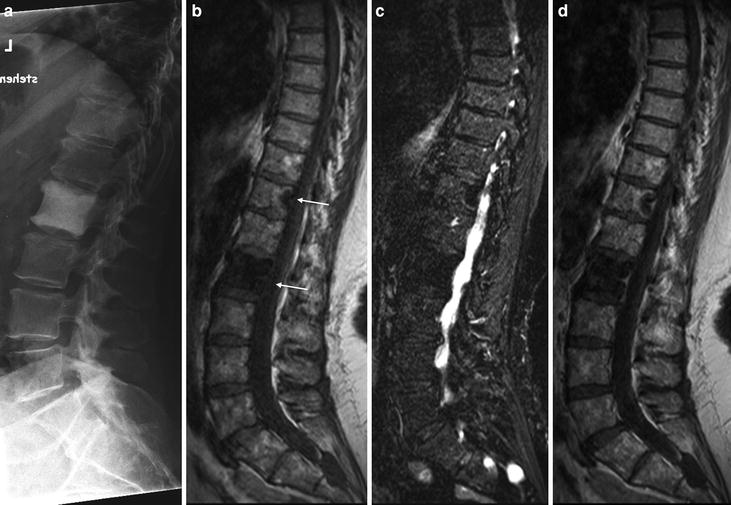

Bone mets are potentially quite damaging. Bone mets can be diagnosed using a variety of diagnostic tools. Over the time it has been ranked as high as 19 739 027 in the world.

For spinal cord compression, please see: Bone tumors and amputation подробнее. Pain can be debilitating and necessitate treatment to help the patient be more comfortable. With rare exceptions, cancer that has spread to.